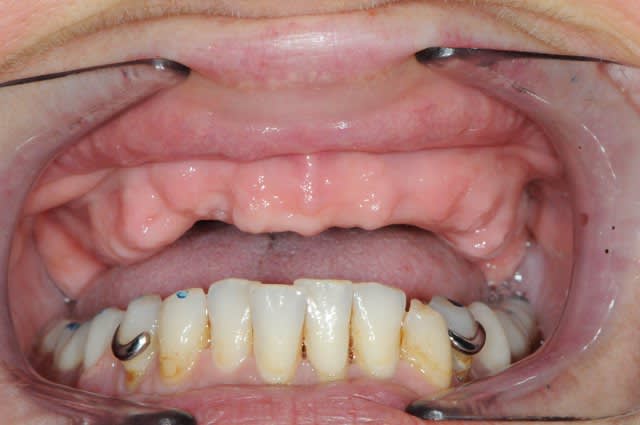

puor commencer complet in situ et guide radio...

Dsc 6073 pcexrz - Eugenol

Dsc 6077 ukfhsf - Eugenol

Smile beach jgh0a1 - Eugenol